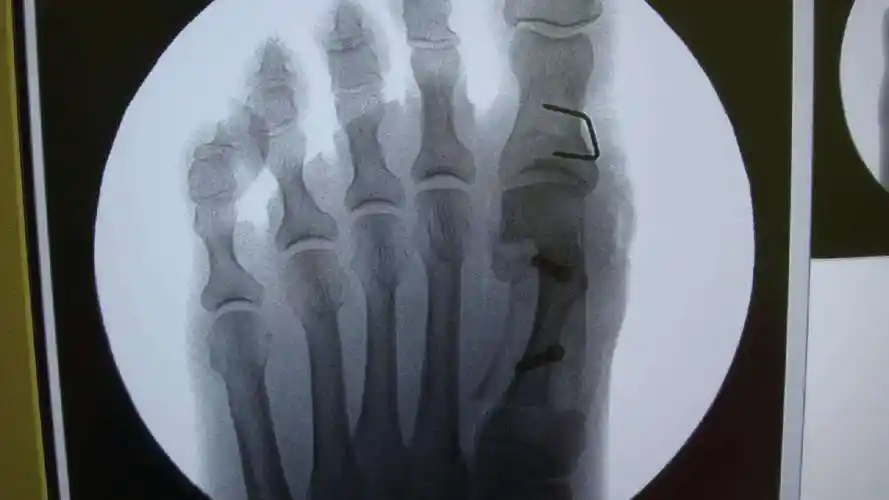

大脚骨scarf akin截骨 - 好大夫在线